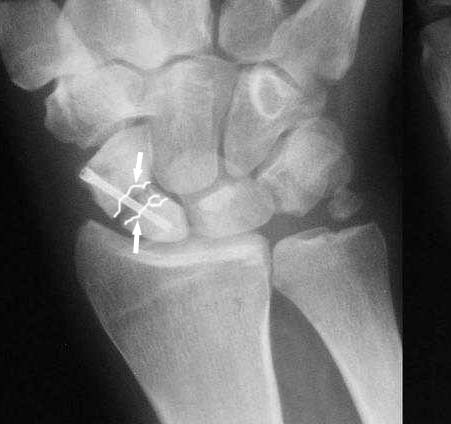

I am not sure if the differential of a nonunion vs. pseudoarthrosis means much in this context. The distal pole of the screw has a lucency, so the

nonunion is most likely unstable and moving. It needs revision. The radial styloid does not have evidence of DJD, so I do not think it needs to be resected. The surgery will probably require an open revision, removal of necrotic bone and soft tissue interposition, and would benefit from some

Ув. Данил! По моему мнению все-таки ложный сустав -склероз отломков (приложение), 5 мес, диастаз. Для подтверждения можно выполнить КТ кистевого сустава (формирование замыкательной пластинки, склероз концов отломков и т.д.,), а так же по КТ можно выявить сохраняется ли подвывих каких-либо костей запястья или нет. При наличии ложного сустава целесообразно будет удалить винт,обработать концы отломков, разрушив замыкательные пластинки и выполнить остеосинтез ладьевидной кости винтом с костной аутопластикой зоны псевдоартроза (либо гидроксиаппатитом...) Гипс 1,5 мес мин. Снимков найти сейчас не получилось. позже дошлю.